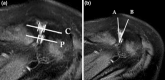

Materials and methods: In a retrospective-monocentric matched pair study, healthy and affected subjects were investigated using T2 MRI scans in the transverse plane. There were two groups, group 1 (n = 151) included healthy asymptomatic adults with no history of trauma. In group 2, we included n = 99 patients with symptomatic AC joints, who underwent arthroscopic AC-joint resection. The central and posterior joint space width and the AC angle were measured. Morphological changes such as cartilage degeneration, cysts and bone edema were noted. Malalignment of the joint was defined as: posterior joint space width < 2 mm in conjunction with an AC angle > 12°. A scoring system consisting of the measured morphologic factors was developed.

Conclusion: Patients with symptomatic AC joints showed a typical pattern of morphological changes on axial MRI scans with early posterior contact of the joint surfaces, reduction of joint space and malalignment as the basis for the development of a scoring system. The MAC score shows excellent test characteristics, and therefore, proved to be both an appropriate guidance for clinical practice as well as an excellent tool for comparative studies and is superior to the assessment of malalignment alone.